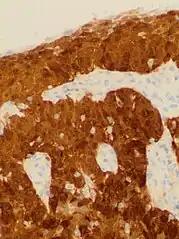

Cervical cancer seen on a T2-weighted sagittal MR image of the pelvis

This large squamous carcinoma (bottom of picture) has obliterated the cervix and invaded the lower uterine segment. The uterus also has a round leiomyoma up higher.